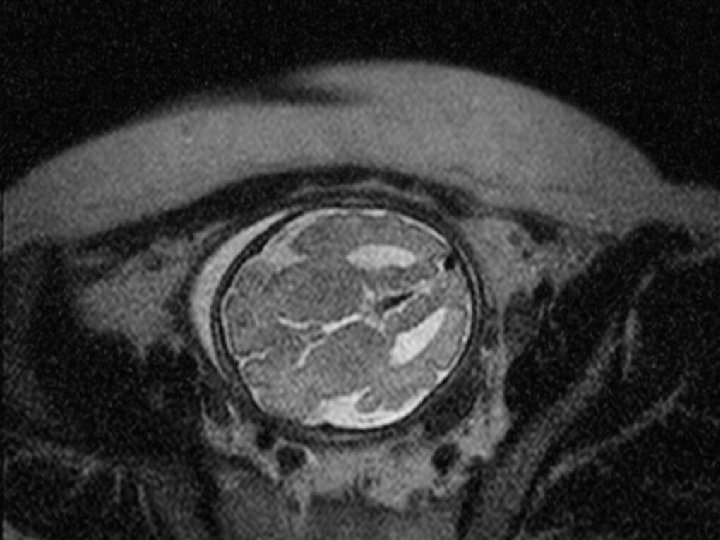

Intracranial Hemorrhage